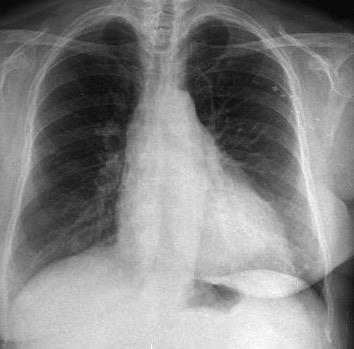

Carcinoma de mama izquierda

Cirugía de Ca .de mama hace 23 añosedema de brazo y ganglio en axila. ¡Metástasis!.